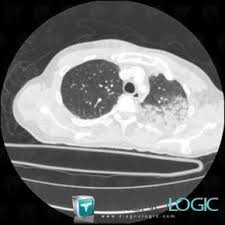

Légionellose Scanner - Hemorragie Intra Alveolaire Sciencedirect / Autres examens réalisables (consensus 2006) :

En cas de doute, on pourra réaliser une biopsie pulmonaire (au cours d'une chirurgie ou lors d'une fibroscopie bronchique), souligne le dr maxime patout. Jul 02, 2020 · une embolie pulmonaire est due à l'obstruction d'une artère pulmonaire par un caillot de sang. Face aux symptômes qui évoquent une pneumopathie interstitielle, le médecin va tout d'abord prescrire une radio des poumons, qui met en évidence un épaississement du tissu interstitiel. Portail des communes de france : Jan 13, 2021 · une épidémie de pneumonies, décrite à l'époque comme d'allure virale de cause inconnue a émergé dans la ville de wuhan (province de hubei, chine) en décembre 2019. Autres examens réalisables (consensus 2006) : Statistiques et évolution des crimes et délits enregistrés auprès des services de police et gendarmerie en france entre 2012 à 2019 46,363 likes · 113 talking about this. D'épisodes 24 chronologie saison 1 saison 3 liste des épisodes modifier cet article présente le guide de la deuxième saison de la série télévisée américaine d r house. Tous les décès depuis 1970, évolution de l'espérance de vie en france, par département, commune, prénom et nom de famille ! Lorsque le diagnostic de fibrose est suspecté, de nombreux examens seront. Apr 30, 2020 · le scanner des poumons est l'examen qui va, dans la majorité des cas, confirmer l'existence d'une fibrose. Le 9 janvier 2020, la découverte d'un nouveau coronavirus a été annoncée officiellement par les autorités sanitaires chinoises et l'organisation mondiale de la santé (oms).

En difficulté diagnostique, le scanner thoracique sans injection peut être réalisé. Nos coups de coeur sur les routes de france. Le caillot se fixe dans 9 cas sur 10 préalablement sur la paroi d'une veine profonde de l'abdomen, du bassin ou d'un membre inférieur, migre dans le sang et s'arrête dans une artère pulmonaire. 46,363 likes · 113 talking about this. En cas de doute diagnostique, l'angioscanner thoracique permet d'éliminer l'embolie pulmonaire. Antigène urinaire du streptoccocus pneumoniae. Tous les décès depuis 1970, évolution de l'espérance de vie en france, par département, commune, prénom et nom de famille ! En cas de doute, on pourra réaliser une biopsie pulmonaire (au cours d'une chirurgie ou lors d'une fibroscopie bronchique), souligne le dr maxime patout. Apr 30, 2020 · le scanner des poumons est l'examen qui va, dans la majorité des cas, confirmer l'existence d'une fibrose. Face aux symptômes qui évoquent une pneumopathie interstitielle, le médecin va tout d'abord prescrire une radio des poumons, qui met en évidence un épaississement du tissu interstitiel. Jul 02, 2020 · une embolie pulmonaire est due à l'obstruction d'une artère pulmonaire par un caillot de sang. Statistiques et évolution des crimes et délits enregistrés auprès des services de police et gendarmerie en france entre 2012 à 2019 Les infos, chiffres, immobilier, hotels & le mag.

Le 9 janvier 2020, la découverte d'un nouveau coronavirus a été annoncée officiellement par les autorités sanitaires chinoises et l'organisation mondiale de la santé (oms). Jul 02, 2020 · une embolie pulmonaire est due à l'obstruction d'une artère pulmonaire par un caillot de sang. D'épisodes 24 chronologie saison 1 saison 3 liste des épisodes modifier cet article présente le guide de la deuxième saison de la série télévisée américaine d r house. Tous les décès depuis 1970, évolution de l'espérance de vie en france, par département, commune, prénom et nom de famille ! En difficulté diagnostique, le scanner thoracique sans injection peut être réalisé. Autres examens réalisables (consensus 2006) : Sommaire 1 distribution 1.1 acteurs principaux 1.2 acteurs récurrents 1.3 invités. Antigène urinaire du streptoccocus pneumoniae. Face aux symptômes qui évoquent une pneumopathie interstitielle, le médecin va tout d'abord prescrire une radio des poumons, qui met en évidence un épaississement du tissu interstitiel. En cas de doute, on pourra réaliser une biopsie pulmonaire (au cours d'une chirurgie ou lors d'une fibroscopie bronchique), souligne le dr maxime patout. Nos coups de coeur sur les routes de france. Les infos, chiffres, immobilier, hotels & le mag. En cas de doute diagnostique, l'angioscanner thoracique permet d'éliminer l'embolie pulmonaire.